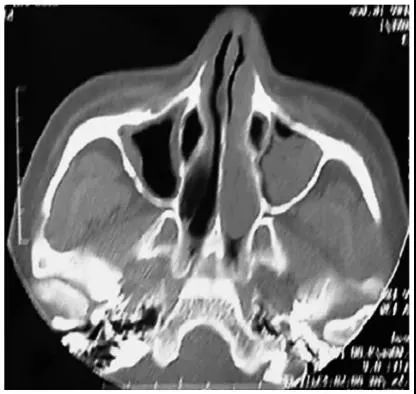

因為鼻腔狹窄,MRI具有較好的軟組織分辨力,能清楚顯示腫瘤范圍及向周圍組織,尤其是對顱內(nèi)的侵犯情況;CT對于顱面部骨性結(jié)構(gòu)的改變顯示更加清楚,故兩者相結(jié)合更有助于腫瘤診斷及分期。有條件的醫(yī)院和患者,還可以做動脈數(shù)字減影血管造影,可以明確腫瘤的血供來源,并行術(shù)前動脈栓塞,減少術(shù)中出血。